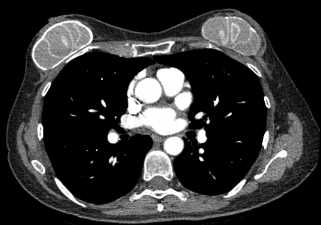

A 58-year-old Brazilian woman was referred for bilateral implant rupture identified on computed tomography (CT) performed to monitor an 8 x 5-mm stable right lower lobe nodule. The patient had a history of bilateral subglandular periareolar breast augmentation performed in Brazil 30 years ago. The operative details and implant type were unknown and irretrievable due to the location and date of the procedure. Over time, the patient developed increasing firmness and tenderness of the breasts. Clinical examination revealed bilateral subglandular breast implants in place, symmetric in size and shape, with Baker Grade 4 capsular contracture. CT imaging showed high-attenuation curvilinear bands throughout both prostheses suggestive of bilateral intracapsular implant rupture (Figure 1). Based on the capsular contracture and highly suggestive CT results for intracapsular implant rupture, surgical intervention was performed.

In the present case, the CT image suggested intracapsular implant rupture due to the presence of what appeared to be linguini signs. However, it was discovered after surgical intervention that these findings were a result of multiple intact small-sized implants whose boundaries resembled linguini signs in the image.